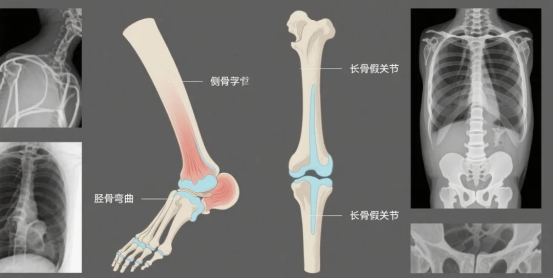

⑤骨骼的特殊变化:骨头出现特殊的生长问题,比如蝶骨发育不良、胫骨弯曲、长骨出现假关节等。